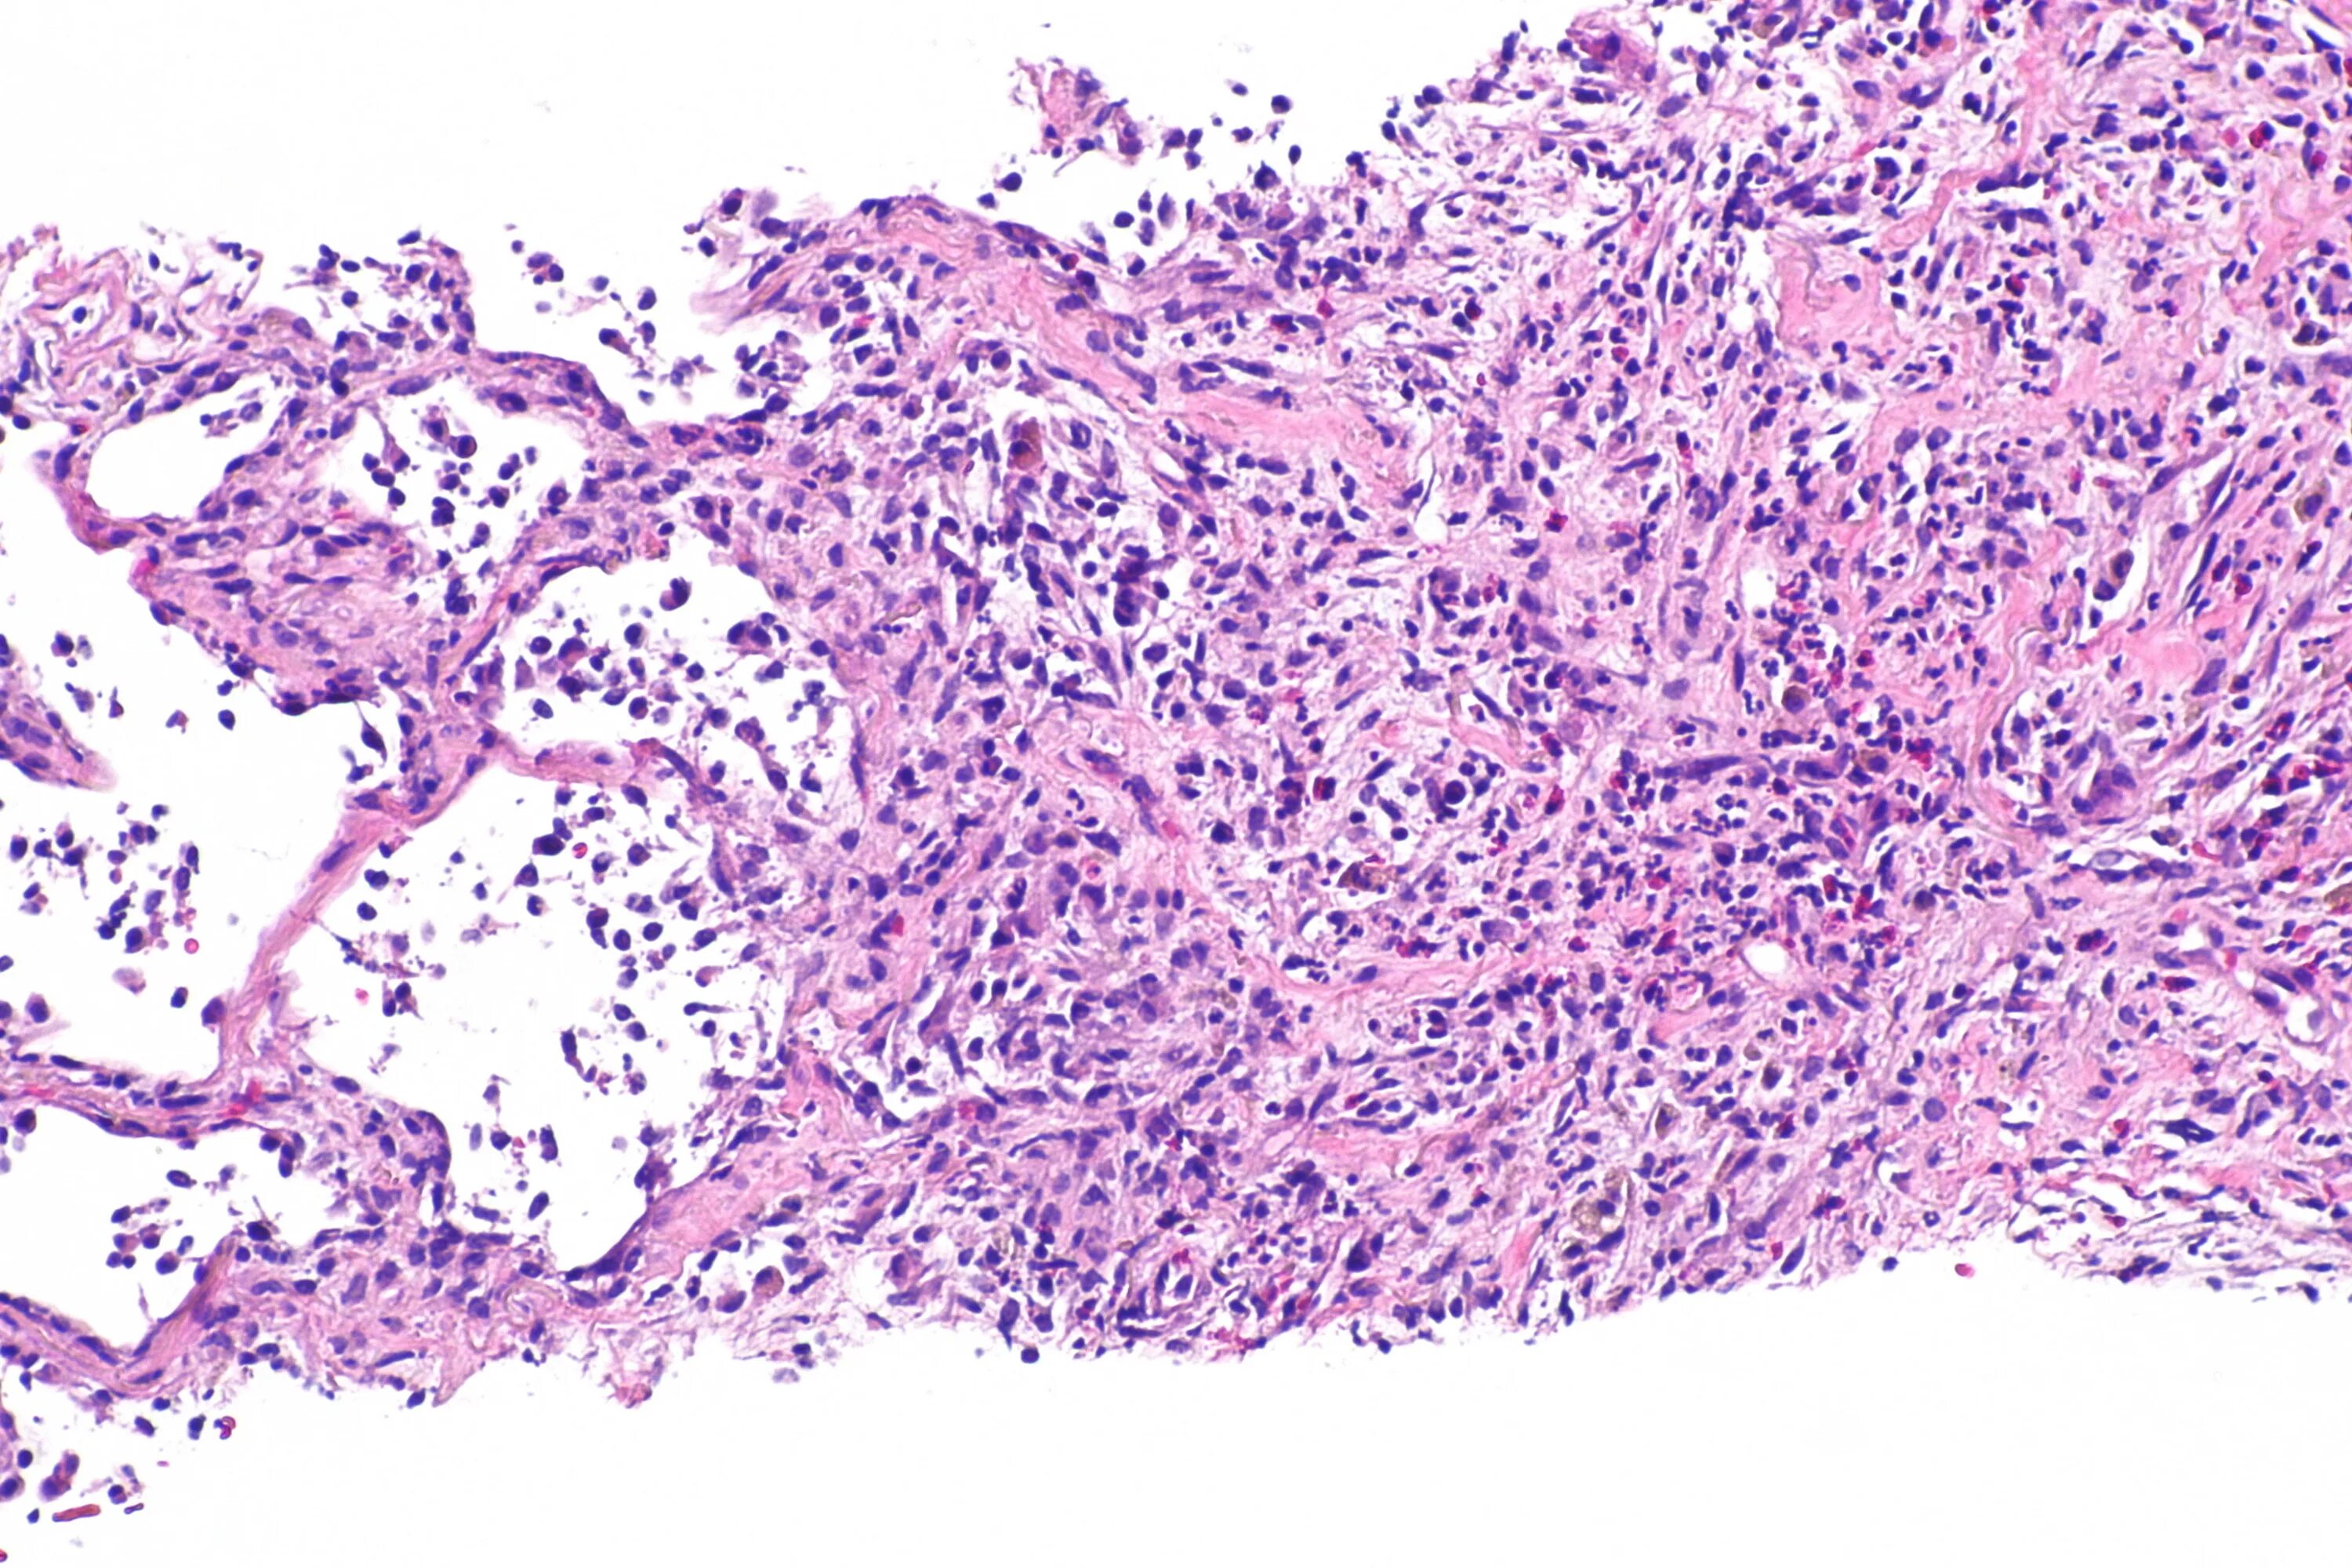

Синусовый гистиоцитоз лимфатического узла